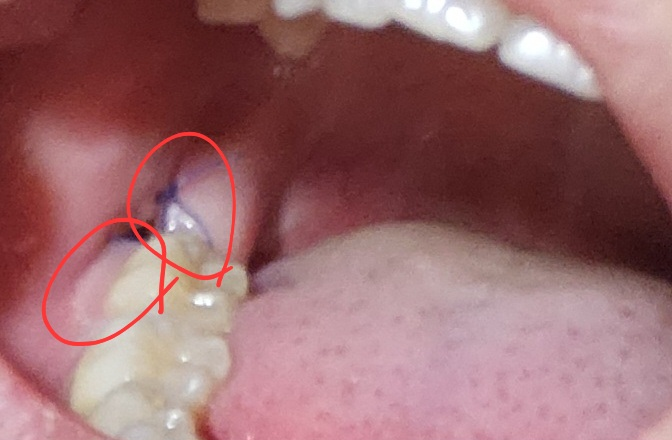

- 사진에 동그라미친 부분 하얗게 있는데 저 부분은 뭔가요?

• 2번 째 사진

2. 하얀 부분은 발치 후 잇몸 치유가 이뤄지는 과정에서 생기는 육아조직입니다.

사진상으로는 염증 없이 잘 낫고 있으며 상피가 자라기 위해 세포가 생기면 하얗게 보입니다.

혈병으로 보이며, 일부러 제거하지는 않아야합니다.

흰색은 잇몸이 아무는 과정에서 생기는 가피일 가능성이 있습니다.